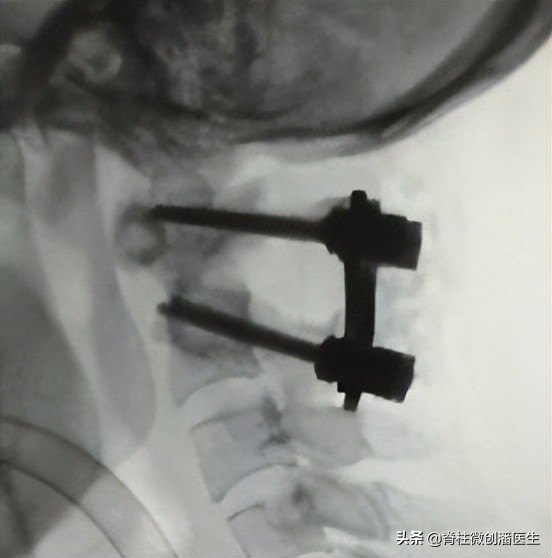

如果旋转性半脱位的持续时间超过3个月,或出现神经损害,或寰枢关节前脱位,则有必要进行寰枢椎后路融合术。术前牵引2-3周以尽可能矫正畸形,术后维持牵引或采用头环背心固定,直至影像学上确认融合为止,一般至少需要6周。